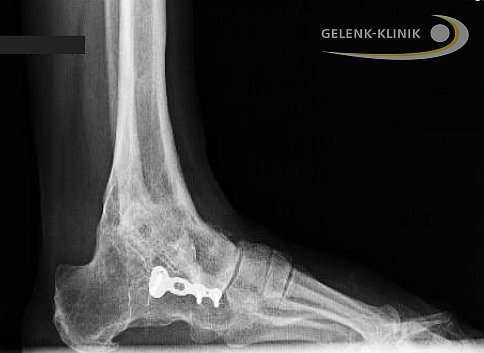

Артродез помогает восстановить безболезненность и потерянную подвижность. Данное вмешательство требует использования специальных винтов и интрамедуллярных гвоздей. Они фиксируют сустав до полной оссификации. © Gelenk-Klinik

Прочное важное для остеосинтеза костное соединение, закрепляется при помощи винтов либо пластин. Артроскопические вмешательства подразумевают лишь микроскопические разрезы на коже. Сохранение мягких тканей является является важным элементов в таком лечении: только при низком рубцевании, в будущем возможно эндопротезирование.

Артродез голеностопного сустава проводится и при использовании интрамедуллярных гвоздей, которые соединяют большеберцовую кость с таранной и пяточной. Артроз нижнего голеностопа и тяжелые травмы пяточной кости требуют проведения данной методики. Применение интрамедуллярных гвоздей для обездвиживания голеностопа приводит ещё и обездвиживанию сустава между пяточной и таранной костью. © Gelenk-Klinik